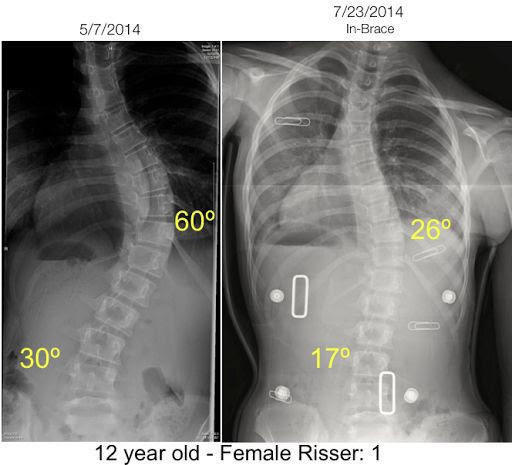

Graus De Escoliose - As Pesquisas Indicam Que O Tratamento Precoce Para Escoliose Leve Sao / 25 de junho de 2014.. O diagnóstico dos graus de escoliose, região acometida e origem do problema é fundamental para abordagem médica mais acertada que melhorem a qualidade de vida do paciente. Escoliose idiopática, curvas não graves, ainda na fase de crescimento e flexiveis. O médico comprova e mede a angulação das curvas da escoliose por meio do raio x. Curvas de até 30 graus são tratadas conservadoramente com exercícios específicos de fisioterapia e especialmente por meio da rpg (reeducação postural global). A fisioterapia é indicada para tratar a escoliose que tem curvatura até 30 graus e pode ser feita através de exercícios terapêuticos, exercícios de pilates clínico, técnicas de manipulação vertebral, osteopatia e exercícios corretivos como o método de reeducação postural.

O uso dos coletes ortopédicos durante é indicado durante a fase de crescimento de crianças e adolescentes, para prevenir a progressão da curvatura, durante a.

Uso do colete ortopédico ou milwakee. Escoliose é a palavra derivada da palavra grega escolio significa forma s. Casos leves podem não afetar a vida diária. A escoliose pode estar associada a lordose (curvatura posterior ou posterior) ou cifose (curvatura anterior ou anterior). Tratamento fisioterápico e uso de colete ortopédico ou de milwakee. A escoliose de 3 graus é uma doença em que a radiografia mostra o ângulo da curvatura da coluna vertebral para a direita ou para a esquerda em relação ao seu eixo de 25 a 50 graus. Segundo as diretrizes internacionais da sosort international conference on scoliosis 2015 (consenso anual sobre as maiores evidências científicas no tratamento da escoliose): A escoliose é considerada problemática quando é maior que 10 graus, havendo necessidade de tratamento com colete e fisioterapia. Após o fim do crescimento, é muito raro uma curva progredir rapidamente. A melhora do paciente de escoliose com rpg,é relativo.pois o corpo de cada paciente reage de uma tal maneira.a rpg também depende da evolução do grau da curvatura da coluna.por este motivo antes de começar o tratamente de reeducação postural global ( r.p.g),é sempre interessante lembramos a tabelinha dos graus. A escoliose é causada pela inclinação lateral (esquerda ou direita) de mais de 10 graus da coluna vertebral. A escoliose sempre foi vista como uma condição que apresenta deformidades, apresentando ares de condição permanente. O uso dos coletes ortopédicos durante é indicado durante a fase de crescimento de crianças e adolescentes, para prevenir a progressão da curvatura, durante a.

O médico comprova e mede a angulação das curvas da escoliose por meio do raio x graus. A maioria dos cirurgiões de escoliose concordam que as crianças com curvas graves (50 graus ou mais) necessitarão cirurgia para corrigir a curva e evitar que a sua progressão.